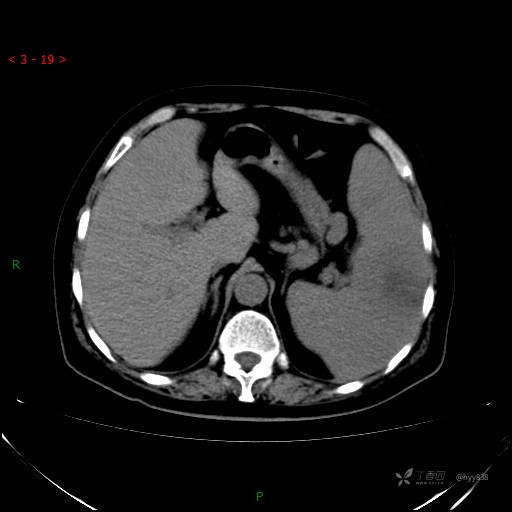

上腹部CT平扫